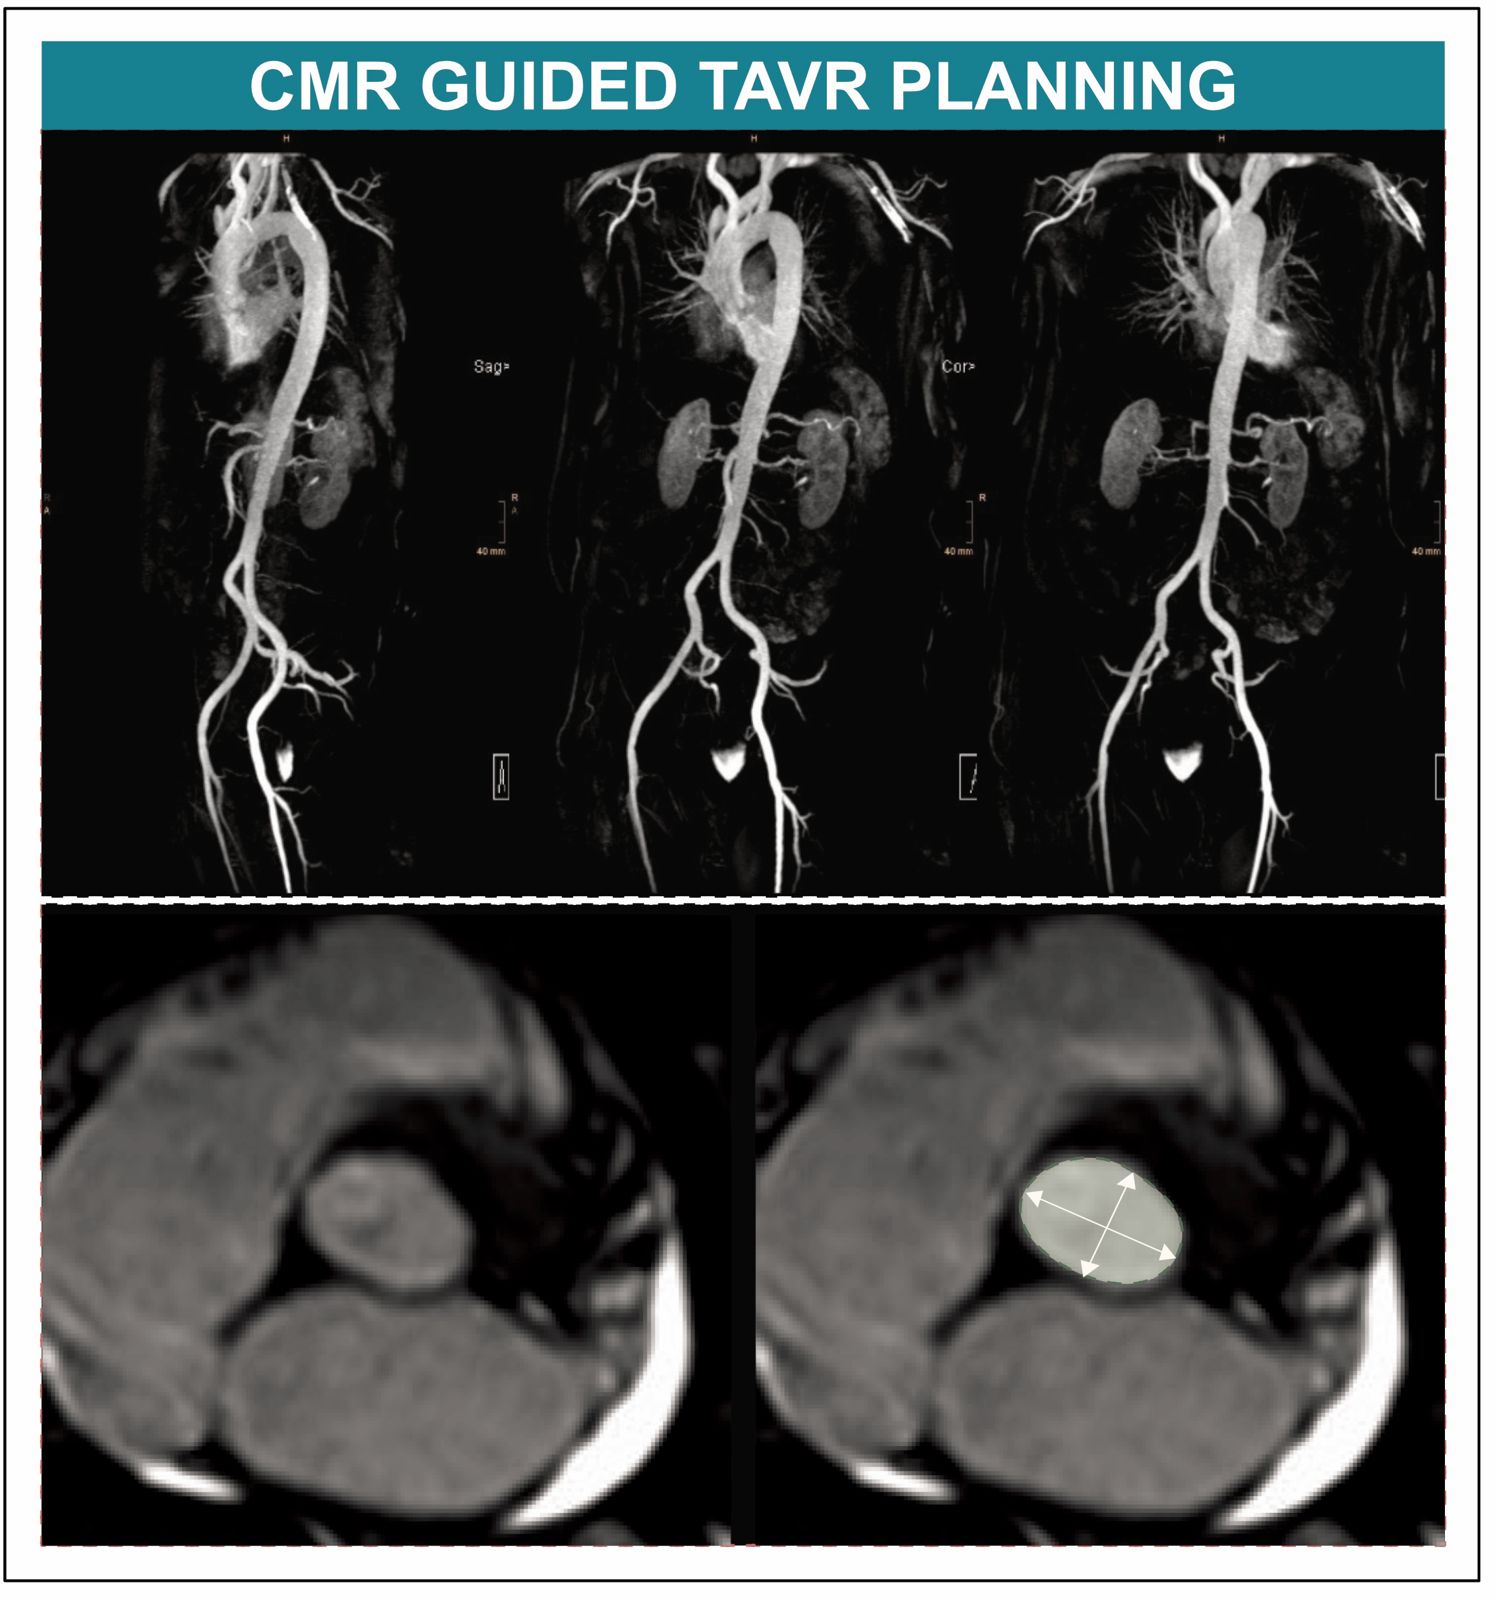

BU: Neue Daten belegen, dass die Kardioale Magnetresonanztomografie bei der Planung einer TAVI keine Nachteile hat. (c)Kardiologie Innsbruck

In einer neuen, kürzlich im anerkannten Fachjournal Circulation veröffentlichen Studie konnte nun erstmals die CMR als gute und klinisch geeignete Alternative für die TAVI-Planung nachgewiesen werden. Für das Kooperationsprojekt zwischen der Univ.-Klinik für Kardiologie und Angiologie und der Univ.-Klinik für Radiologie wurden TAVI-Kandidat:innen an den Herzzentren in Innsbruck und Wels randomisiert und einer CMR-gesteuerten oder einer CT-gesteuerten TAVI-Planung zugeführt. „In der Kohorte mit jenen Patient:innen, die sich einer TAVI unterzogen hatten, konnten wir feststellen, dass die CMR-gesteuerte TAVI der CT-gesteuerten TAVI im Hinblick auf den Implantationserfolg nicht unterlegen war und daher als Alternative zur TAVI-Planung in Betracht gezogen werden kann“ bestätigt Erstautor Martin Reindl, der diese positiven Erkenntnisse gemeinsam mit der von Bernhard Metzler geleiteten Arbeitsgruppe Kardio-MRT am diesjährigen ESC Kongress, dem weltweit führender Kongress im Bereich Kardiologie, in der prominenten „Late Breaking Science“ Session vorstellen konnte.